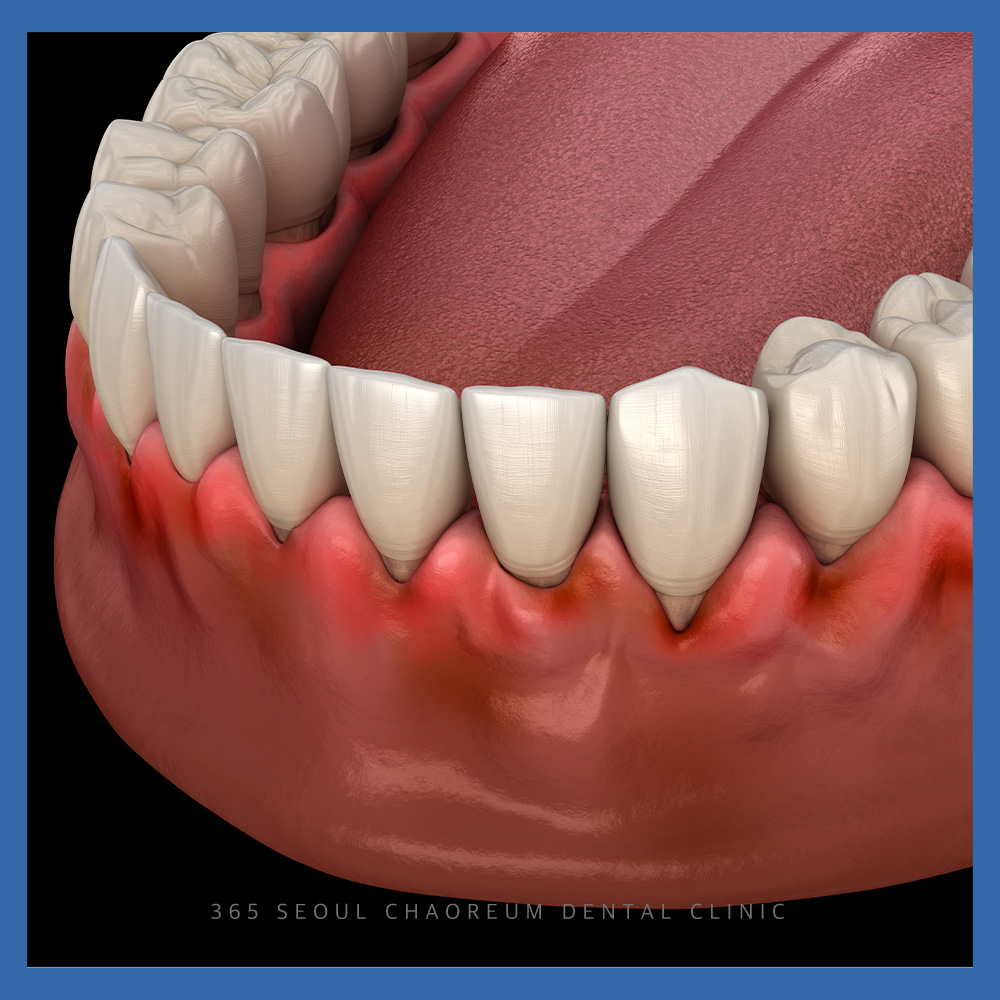

특히 아래 앞니는

겉으로 잘 드러나는 부위인 만큼

심미적인 역할도 크지만,

상대적으로 치조골 두께가 얇아

치주 질환의 영향을 받기 쉬운

위치이기도 합니다.

치주염이 진행되면

잇몸 염증을 넘어 치아를 지지하는

치조골까지 서서히 소실될 수 있습니다.

확인해 보니,

앞니가 하나 소실된 상태이며

그로 인해 잇몸뼈의 폭이

좁아져 있는 것을 확인할 수 있었습니다.

그리고 인접 치아의 잇몸이 내려가 있고,

잇몸이 부어있는 것을 확인할 수 있었는데요.

이로 인해,

치주염의 진행 가능성을

배제할 수 없는 상태였습니다.